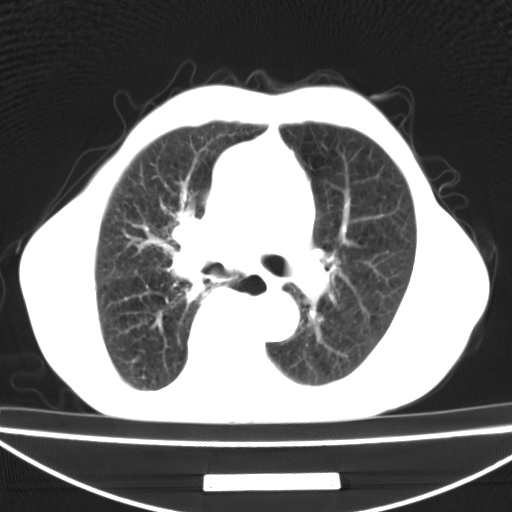

标题: CT13796:请会诊右上费病变!

患者男80岁,反复咳嗽多年,咳喘伴咯血1月

右上肺周围型肺癌伴肺门淋巴结转移.右上肺继发型肺结核.

右上肺周围型肺癌伴肺门淋巴结转移

右肺上叶占位性病变,考虑周围型肺癌,肺门淋巴结转移。要是能提供更多的临床资料就好了,以供鉴别诊断。

右肺尖周围型肺癌伴肺门淋巴结肿大

右肺上叶占位性病变,考虑周围型肺癌,肺门淋巴结转移。

右上肺周围型肺癌伴肺门、纵膈淋巴结转移

考虑为:右肺上叶肺癌伴阻塞性肺炎、右肺门及纵膈淋巴结转移。